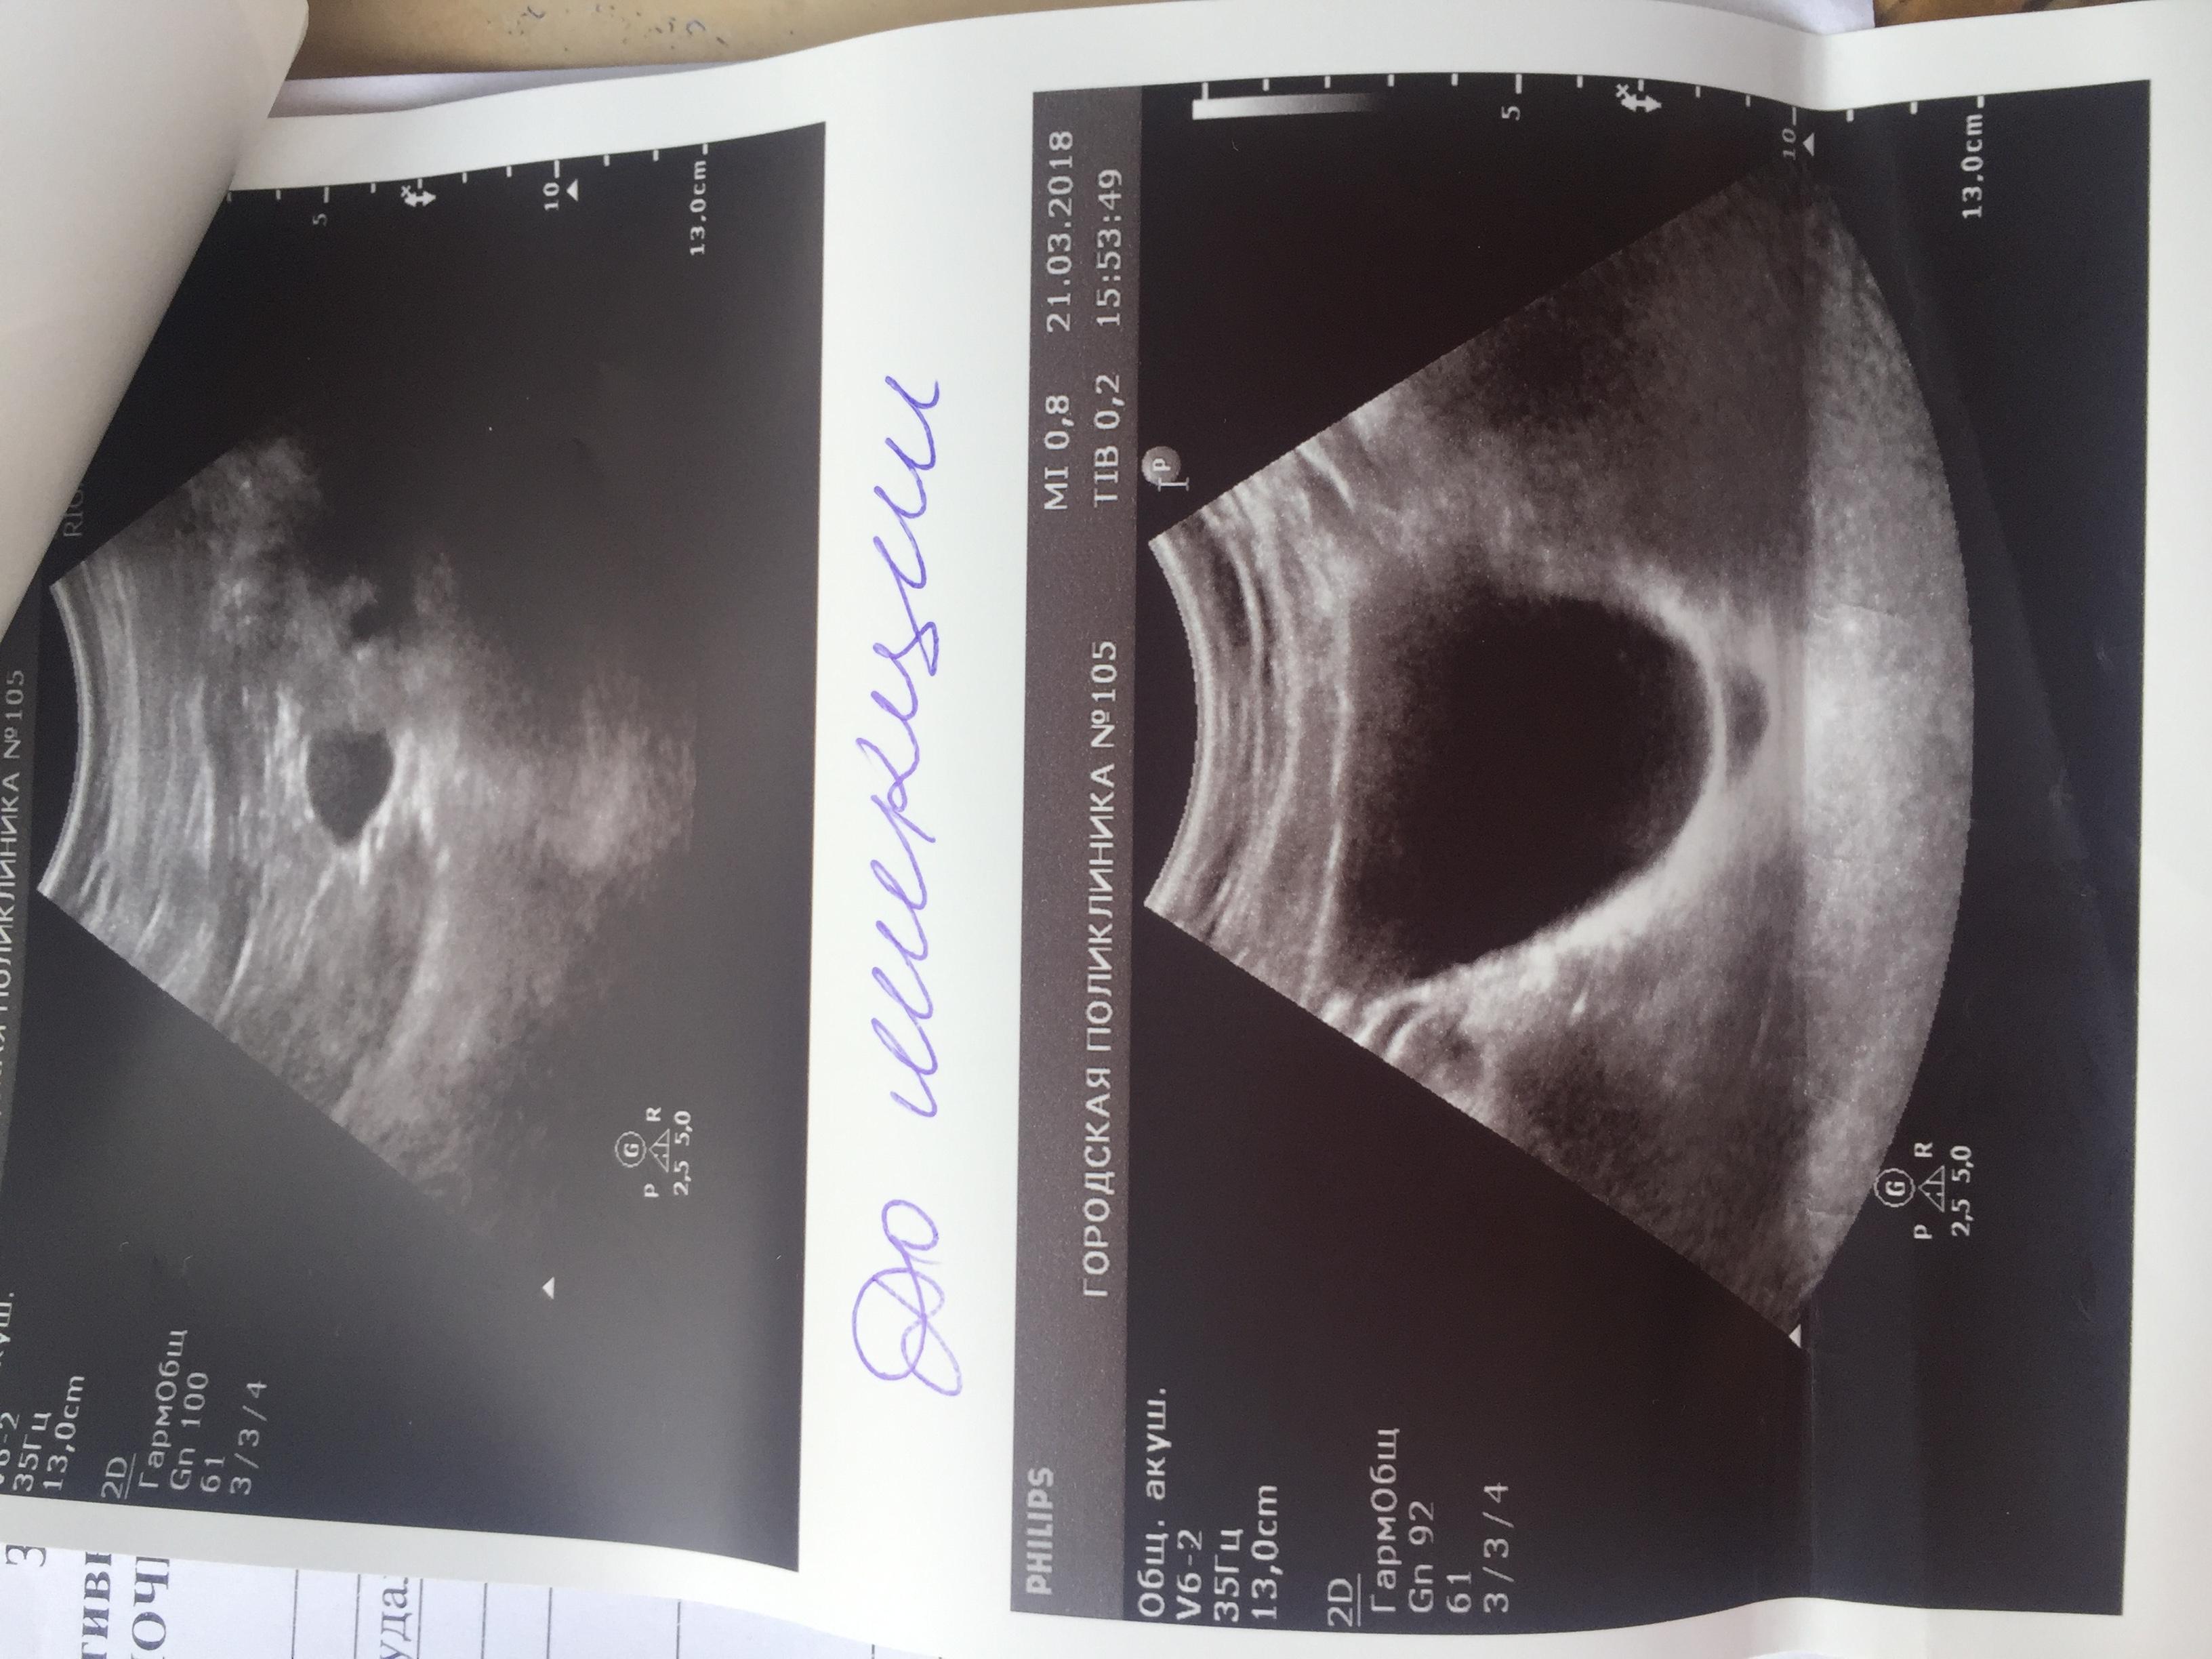

Здравствуйте. С Рождения гидронефроз левой почки , была удалена в декабре 2009 года. Анализы мочи и биохим анализ крови все показатели всегда в норме. Ребёнку 8 лет, сейчас одно УЗИ показывает размер почки 112 на 56, лоханка 16 мм. Другое узи сделанное через день показало: размер почки 78 на 30 , лоханка 7 мм. Паренхима на обоих узи 13 мм. Так же было сделано исследование УЗДГ почки ( все в норме, отклонений нет) Не можем понять почему такая разница по УЗИ где правда ? Как нам с этим разобраться .